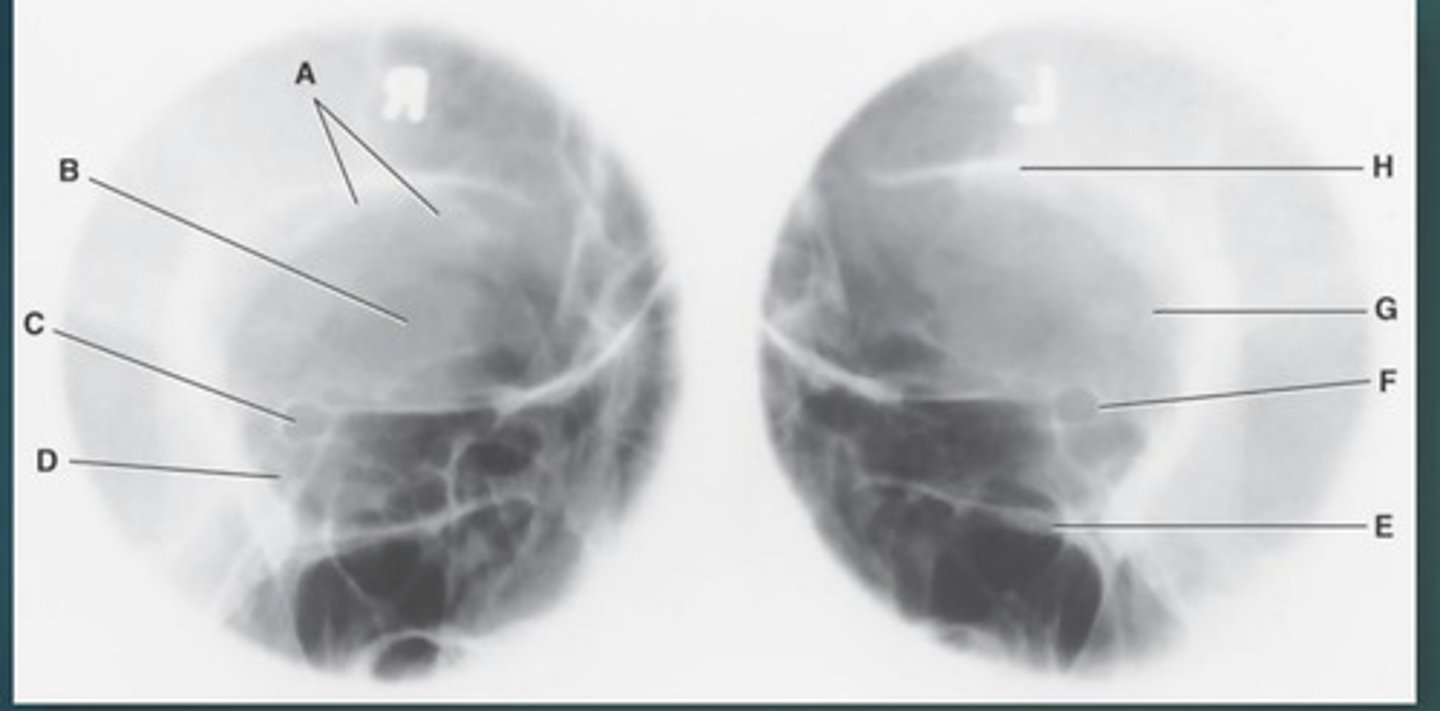

Lateral sinus

What position?

L. Orbital roofs

A.

L. Greater wings of sphenoid

B.

sella turcica of sphenoid

C.

L. Sphenoid sinus

D.

L. Rami of mandible

E.

L. Maxillary sinuses

F.

L. Ethmoid sinuses

G.

L. Frontal sinuses of frontal bone

H.